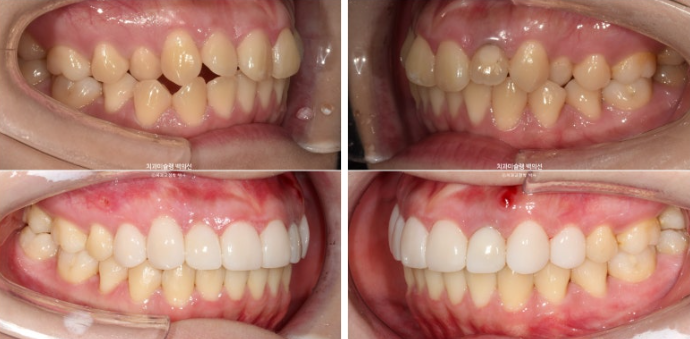

환자가 고치고 싶은 것은 배열, 교합, 거미스마일(잇몸미소) 마지막은 비대칭 입니다.

엑스레이 검사 결과 뼈의 비대칭은 경미하나 상하 치아중심선이 어긋나있어서 이 부분 개선을 원하셨습니다.

교합은 거꾸로 물리는 어금니 반대교합도 있고, 뜨는 부분도 있고 앞니 하나는 신경치료 후 변색이 되어 있습니다.

작은어금니가 입천장으로 들어가 있어 반대교합 상태였습니다.

앞니 배열은 좋아졌지만 중심선이 아직 아쉽고 앞니 높낮이 단차의 개선이 좀더 필요합니다.

어금니 교합은 좋습니다.

배열도 대부분 완료되었습니다.

중심선은 이제 정확히 맞습니다.

맞아진 중심선과 배열의 개선이 보입니다.

반대교합의 개선이 됩니다.